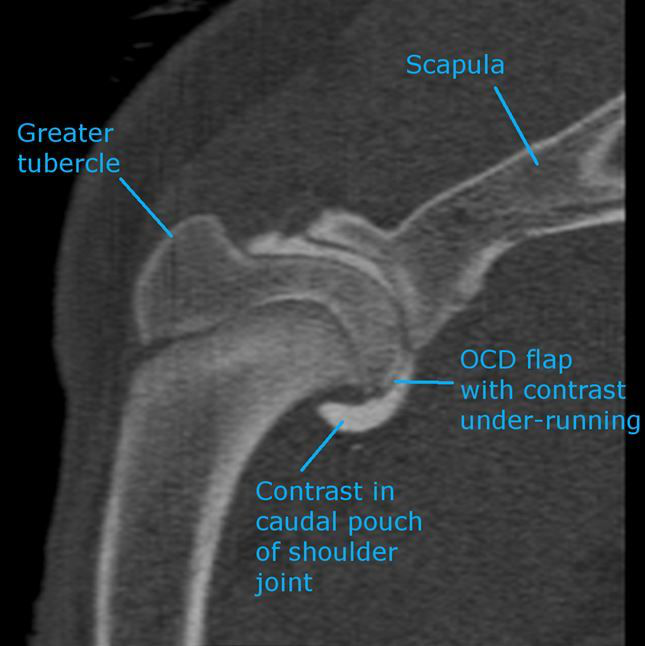

An image labelling an example of osteochondritis

Osteochondritis dissecans is a disease that affects a dog’s joints – at the shoulders, the elbows, the hips, the knees, and the ankles. When a dog has this condition, the cartilage of the joints gets inflamed and separates from the bone of the joints. The inflamed cartilage then continues growing, unattached from the bone, which causes a big buildup of thick, inflexible cartilage in the joint.